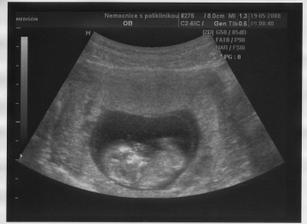

Na první utz až ve 12.tt

UTZ ve 12.tt bylo krásné,Honzíček řádil jako ďábel 😀 Už byli krásně vidět ručičky,nožičky,no krásné mimuško 🙂 Navíc mě ošetřoval doktor - černoušek a já si tak říkala,kdyby tenhle doktor mě rodil..